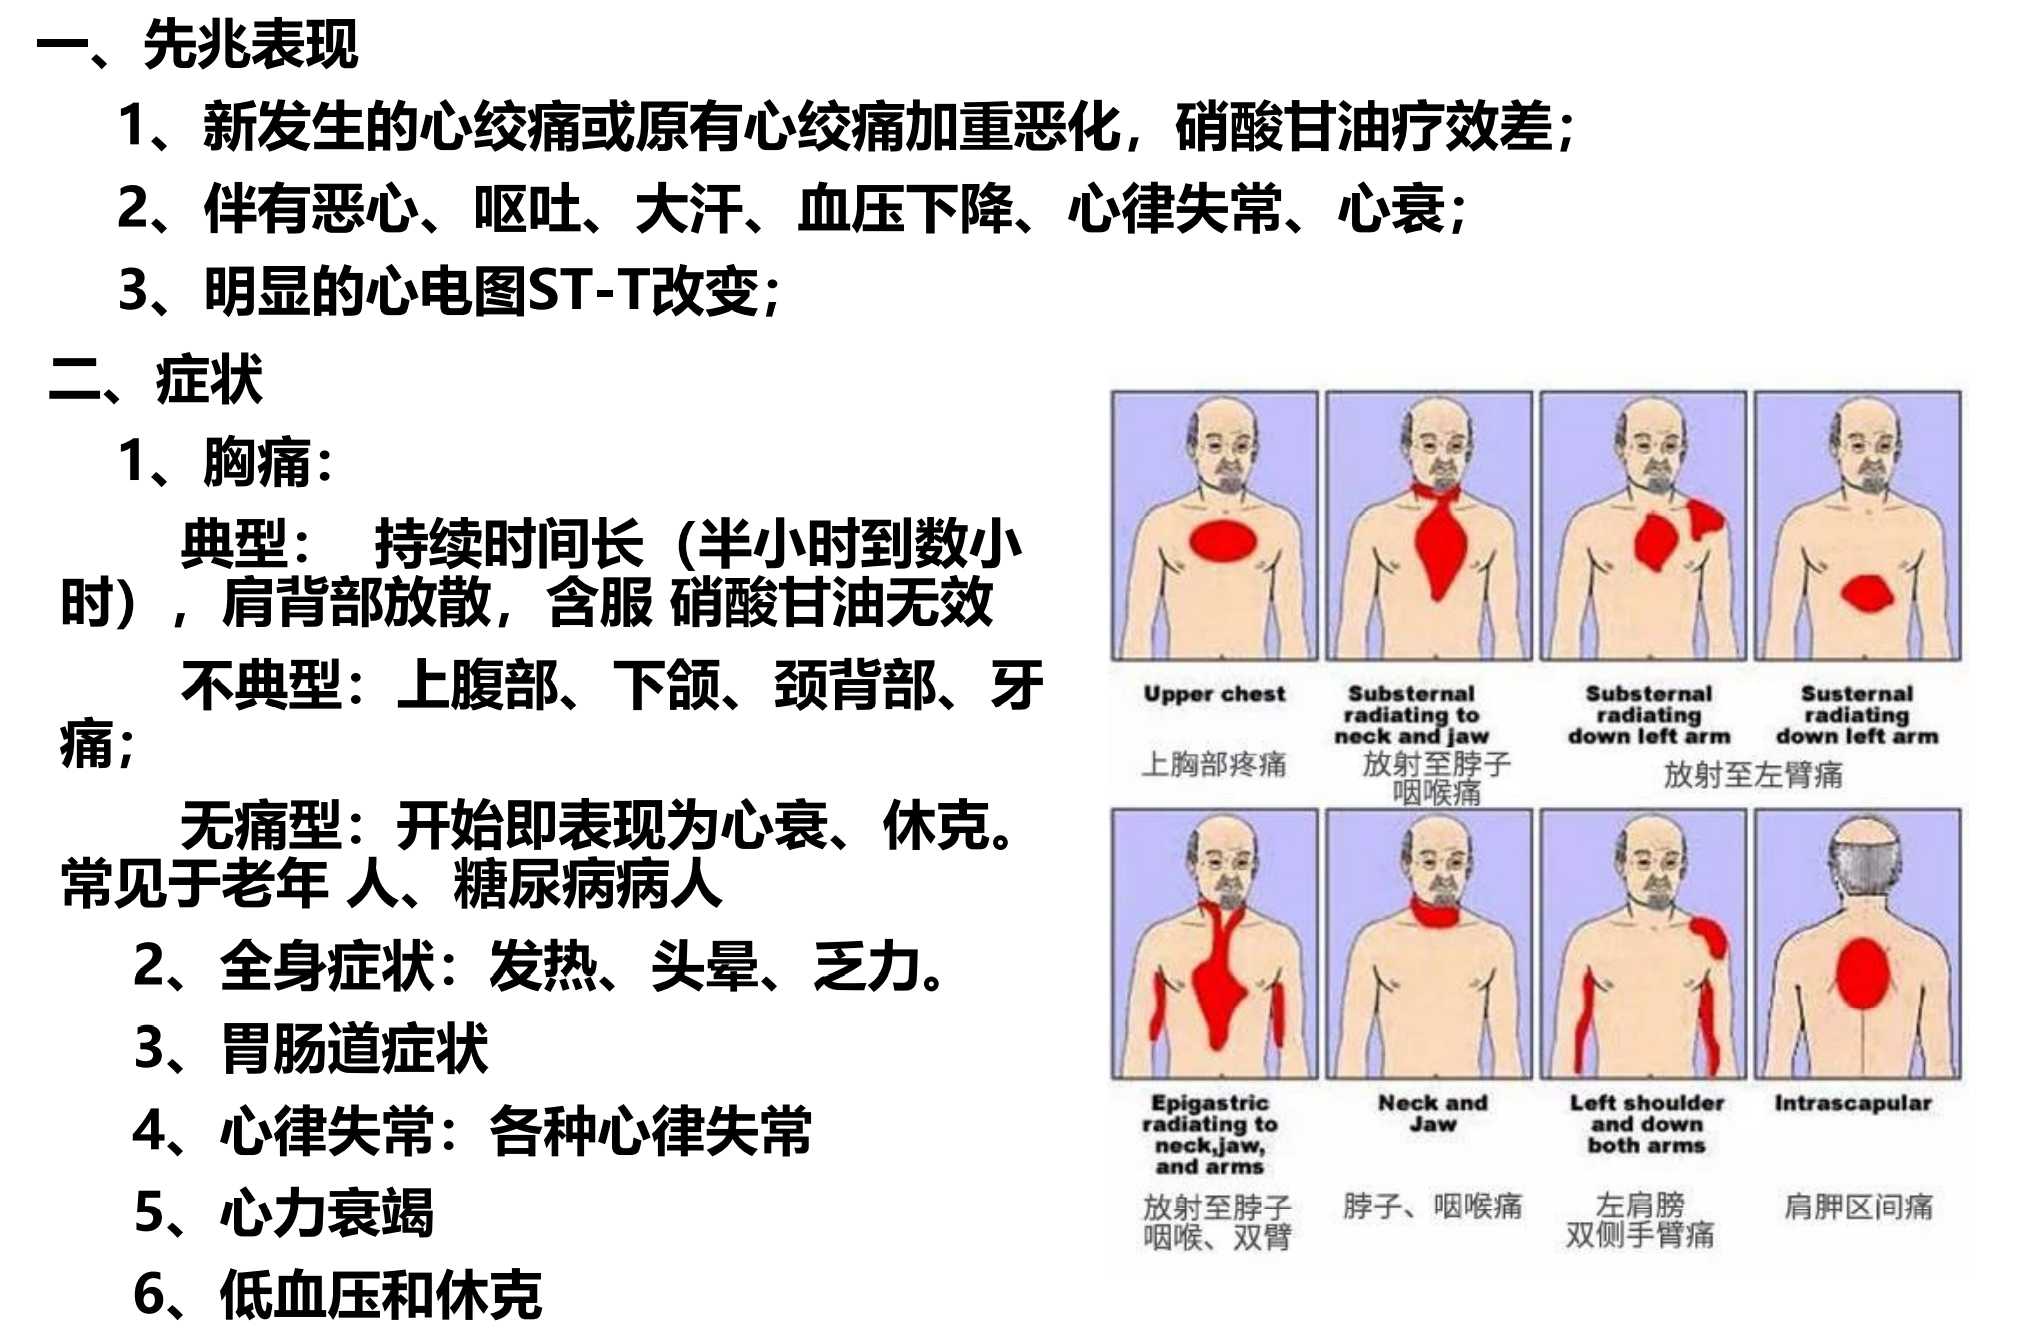

12. 人类的第一杀手——冠心病和心脏运动康复

急性心肌梗死概念与临床特点

急性心肌梗死概念:

由于冠状动脉供血急剧减少或中断,使相应的心肌出现严重持久的缺血而发生的心肌坏死。

临床特点:

持久剧烈胸痛、血清心肌酶升高、心电图系列演变。常伴有心律失常、心力衰竭、休克甚至猝死。

病因和发病机制

一、基本病因:

冠状动脉粥样硬化(个别为冠状动脉痉挛、炎症、先天性畸形、栓塞)→严重狭窄

二、诱因:饱餐、睡眠、大便、 情绪激动等。

临床表现

治疗

原则:保护和维持心功,挽救濒死心肌,缩小梗塞及缺血范围,防治心律失常、心衰及各种并发症。

重点